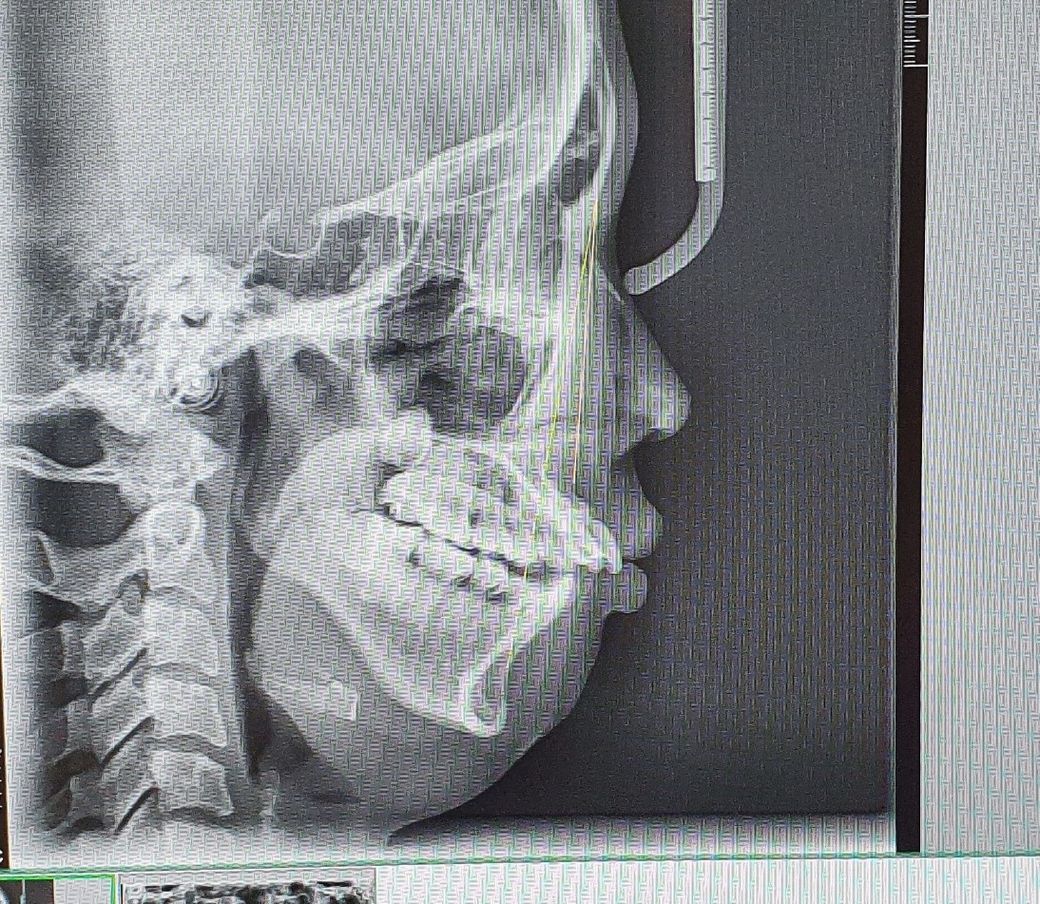

과개교합으로 교정중인데

윗 대문앞니가 뿌리도약해서 어금니발치보다 앞니발치가 낫겠다는 얘길들었고

오늘 앞니를 뽑았습니다.

그런데 튀어나와있던 앞니가 들어가니

윗입술도 자연스레 덜 튀어나와지면서

인중이 길어보이고 원숭이같아요

사진 순서 조정이 안 되는데, 위 사진들이 발치 전 사진들입니다

발치 전 후 안모에서 특별한 차이를 보이지는 않는 것으로 판단됩니다. 해당 치과에 여쭤보시는 게 좋겠습니다.

교정을 하고 계신상태라면 아직은 판단하기는 어렵습니다. 아무래도 치아를 뺀상태이기 떄문에 어색하셔서 그렇지 크게 문제가 잇어 보이진 않아 보입니다.

사진상으로 크게 문제가 되거나 이상해보이지는 않습니다. 미적인 부분은 개인마다 기준이 다르기며, 발치교정시 외모에 다소 변화가 생길 수 있습니다.